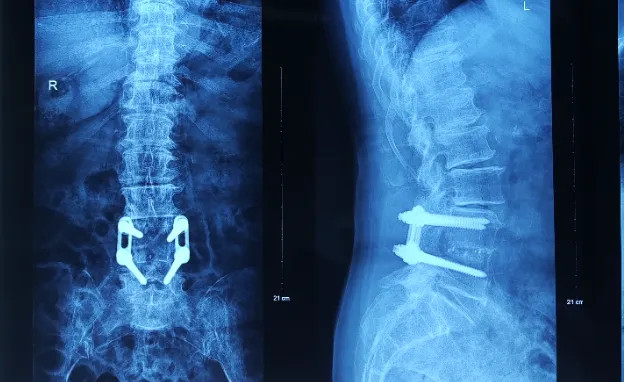

(患者术前X光片)

71岁的邱女士与福州有着特殊的医患情缘。22年前,她因腰椎滑脱在黄播 接受L4-5节段Opus钉板系统复位固定手术,术后完全康复并保持良好生活状态。然而近两年逐渐加重的双下肢麻木无力最终发展为无法站立、二便失禁,辗转粤港澳多家医院均因无法处理“古董级”内固定而束手无策。